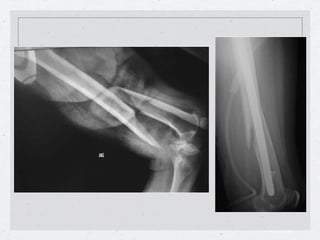

Callo vicioso en los tres planos.

Callo vicioso y artrosis en varo: doble osteotomía

Callo vicioso enlos tres planos.

• 23.

Callo vicioso yartrosis en varo: doble osteotomía